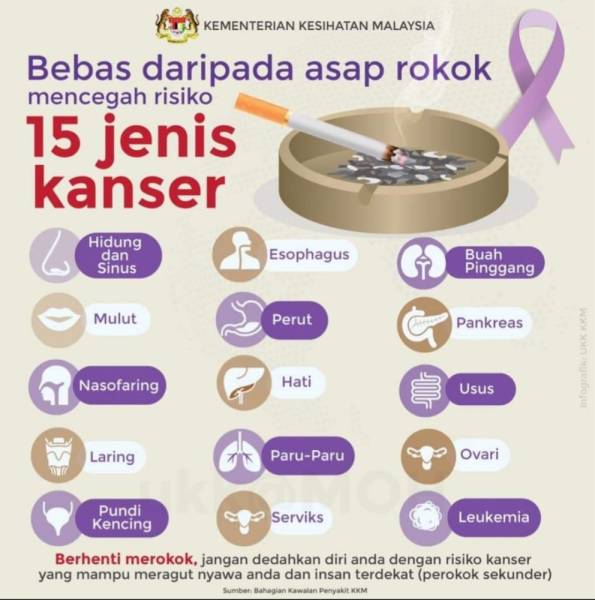

Waspada 15 Jenis Kanser Akibat Merokok

Waspada 15 Jenis Kanser Akibat Merokok